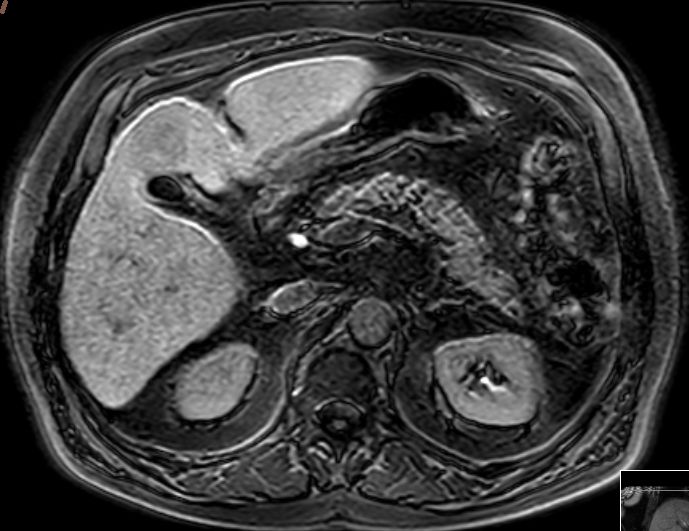

| intrahepatische Filiae | 68-jähriger Mann mit bekannter Leberzirrhose nach Alkoholabusus.

Im CT mehrere hypervaskuläre Herde gesehen.

Im MR beste Darstellung auf den Spätaufnahmen nach leberspezifischem Kontrastmittel in der hepatobiliären Ausscheidung.

Unterhalb der Zwerchfellkuppel links subkapsulär ventral gelegener Herd im 2. Segment 34 mm.

In der koronaren Schichtung im 8.Lebersegment ein 8,5 mm kleiner signalabgesenkter Leberherd.![]() |